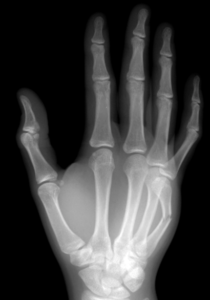

Le 5eme métacarpien peut être fracturé au niveau de sa base, de sa diaphyse (corps de l’os) ou de sa tête.

Fracture de la tête, de la diaphyse et de la base du 5e métacarpien

La radiographie réalisée met en évidence la fracture. Un scanner peut être nécessaire pour obtenir une meilleure analyse de la fracture.